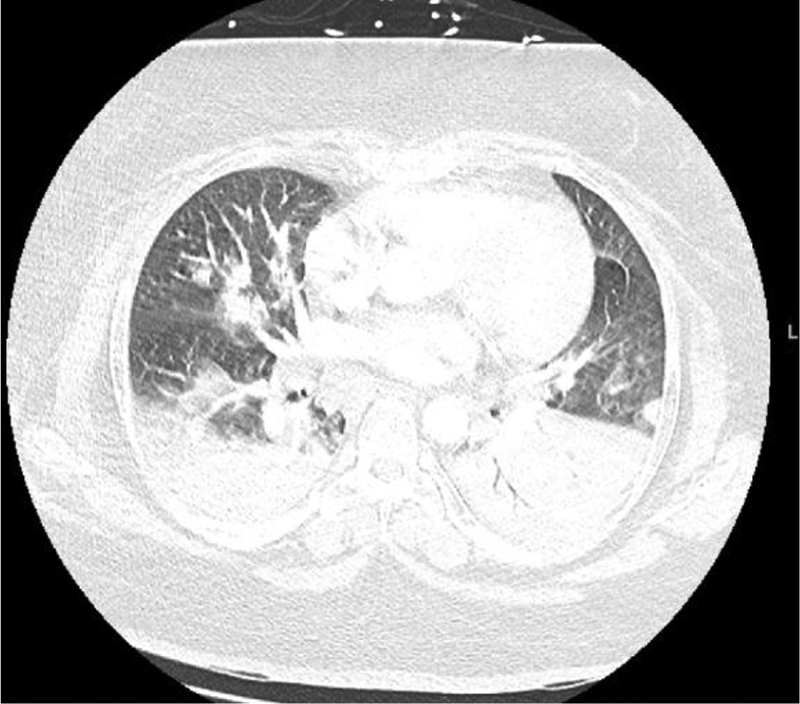

On day 4 of admission, the patient had worsening oxygen requirements throughout the evening and was switched from high-flow nasal cannula to BiPAP (bilevel positive airway pressure). She was saturating 80% with BiPAP settings of FiO2 of 100%, respiratory rate in the 30s, and heart rate sustaining 120s. An arterial blood gas showed a pH of 7.38, PCO2 of 42.1, PO2 of 44 and had a P/F ratio of 49 on BiPAP of FiO2 of 100%. A chest x-ray indicated diffuse bilateral pulmonary opacities (Figure 3). Due to the patient’s being in respiratory distress and refractory hypoxia, she was emergently intubated and brought to the intensive care unit. She was in respiratory distress syndrome (ARDS) secondary to pancreatitis and viral pneumonias. She was started on decadron 10mg IV q12h, IV Zosyn 3.375 gm q8H, and lung protective ventilation strategies. Inflammatory ESR and CRP were also moderately elevated at 47 and 189 respectively, and ferritin was 176.1. Beta-D-Glucan test and sputum culture were negative.

Figure 3

Figure 3. Chest X-ray prior to intubation, indicating bilateral pulmonary opacities.